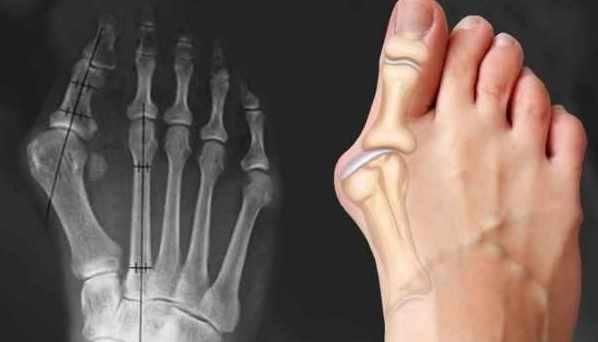

9. Массаж при вальгусной деформации стопы (Александр Иванов)

[​IMG]

Новый онлайн-курс по массажу при проблемах связанных с искривлением большого пальца стопы, образованием "шишки", "косточки" на ноге, плоскостопии и сопутствующих патологиях

Для кого предназначен – для опытных специалистов массажа, начинающих массажистов для расширения массажного кругозора, для любителей массажа и мануальной терапии с целью оздоровления организма в домашних условиях.

Автор курса - профессиональный массажист, автор методики Артикуляционно-рефлекторного массажа, Александр Иванов.

Урок №1. Стопа человека. Анатомические особенности и ориентиры массируемой области

Урок №2. Кости стопы и голени. Обоснованность манипуляций с костями и суставами при hallux valgus

Урок №3. Нервы нижней конечности. Биомеханика периферических нервов, отражение на развитии патологии

Урок №4. Система большого пальца стопы. Вальгусная деформация, механизм развития патологии, биомеханика

Урок №5. Методика и техника массажа при вальгусной деформации большого пальца стопы. Протокол работы

Урок №6. Самокоррекция стопы при вальгусной деформации и плоскостопии